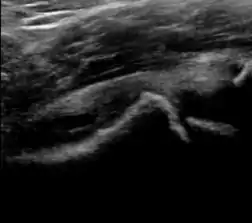

During childhood, ultrasound is a quick method to assess hip pain and quite often may be used to avoid use of irradiating techniques, such as radiography or CT. Ultrasound allows evaluation of joint effusion, synovial thickening and neovascularity, the bone/cartilage contour, and the femoral head-neck alignment. Although sonography is extremely sensitive in detecting increased synovial fluid, it is nonspecific and cannot be used with accuracy to determine the type of fluid. Transient synovitis of the hip, despite being the most frequent cause of pain in children between 3 and 10 years, remains a diagnosis of exclusion. It usually shows anechoic fluid, but echogenic fluid can also be found. The effusion is considered pathologic when it is measured at >2 mm in thickness. The differential diagnosis is wide, including osteomyelitis, septic arthritis, primary or metastatic lesions, LCPD, and SCFE. Discrimination from septic arthritis is challenging, often requiring joint aspiration. In septic arthritis, US is able to demonstrate a hip joint effusion, synovial thickening, and cartilage damage, although the appearances are nonspecific.[1]

Figure 12:

- Normal ultrasound appearance of the femoral head-neck junction.

- Joint effusion in transient synovitis of the hip.

- Flattening of the femoral head in a patient with Perthes disease.

- Step in the femoral head-neck junction in a patient with SCFE.